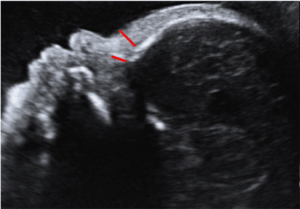

Em 2014 Figueras e Gratacós propuseram uma classificação para os casos de restrição de crescimento intra-uterino baseada em um estadiamento progressivo. Uma vez que um feto pequeno é identificado (isto é, seu peso estimado está abaixo do 10º percentil), um estudo dopplerfluxométrico deve ser realizado. Os vasos a serem investigados são as artérias uterinas, a artéria umbilical, a artéria cerebral média devendo-se calcular a relação cérebro-placentária. Nos fetos com alteração na artéria umbilical, o ducto venoso e a cardiotocografia computadorizada devem ser realizados quando estiverem disponíveis. Abaixo você encontra o estadiamento proposto e também poderá usar a nossa Calculadora de Doppler para estadiamento dos casos de restrição de crescimento intra-uterino.

Restrição de Crescimento Estadio I – O Doppler das artérias uterinas, umbilicais, cerebral ou a relação cérebro-placentária estão alterados. Na ausência de outras anormalidades, as evidências sugerem um baixo risco de deterioração fetal antes do termo. A indução do parto além de 37 semanas é aceitável, mas o risco de sofrimento fetal intraparto é aumentado. A indução cervical com cateter de Foley também é recomendada. O monitoramento semanal parece razoável.

Restrição de Crescimento Estadio II – Este estadio é definido pela velocidade diastólica zero na artéria umbilical ou Doppler do istmo aórtico reverso. Embora a evidência para diástole zero da artéria umbilical seja mais forte do que para o istmo aórtico reverso, a evidência observacional sugere uma associação entre este último e o neurodesenvolvimento anormal, de modo que ambos os critérios se tornam uma única categoria. O parto deve ser recomendado após 34 semanas. O risco de cesárea de emergência na indução do parto vaginal excede 50% e, portanto, a cesárea eletiva é uma opção razoável. O monitoramento duas vezes por semana é recomendado.

Restrição de Crescimento Estadio III – Este estadio é definido pela velocidade diastólica reversa na artéria umbilical ou ducto venoso com índice de pulsatilidade maior que o percetil 95. Há uma associação com um maior risco de natimorto e problemas neurológicos. No entanto, como os sinais que sugerem um risco muito alto de natimortalidade em alguns dias ainda não estão presentes, parece razoável atrasar o parto eletivo para reduzir ao máximo os efeitos da prematuridade grave. Sugere-se que o parto seja realizado por cesariana após 30 semanas. Recomenda-se o monitoramento a cada 24–48 h.

Restrição de Crescimento Estadio IV – Existem desacelerações espontâneas de frequência cardíaca fetal, Short Term Variation (STV) reduzido (<3 ms) na cardiotocografia computadorizada ou fluxo atrial reverso no Doppler do ducto venoso. A desaceleração espontânea da frequência cardíaca fetal é um sinal grave, normalmente precedido pelos outros dois sinais e, portanto, raramente é observada, mas se persistente pode justificar uma cesárea de emergência. A cardiotocografia computadorizada e o ducto venoso estão associadas a riscos muito elevados de natimortalidade nos próximos 3-7 dias e invalidez. O parto deve ser realizado após 26 semanas por cesariana em centro terciário sob tratamento com esteróides para maturação pulmonar. A sobrevida livre de sequelas excede 50% somente após 26–28 semanas e, antes desse limite, os pais devem ser aconselhados por equipes multidisciplinares. Monitoramento a cada 12-24 h até o parto é recomendado.